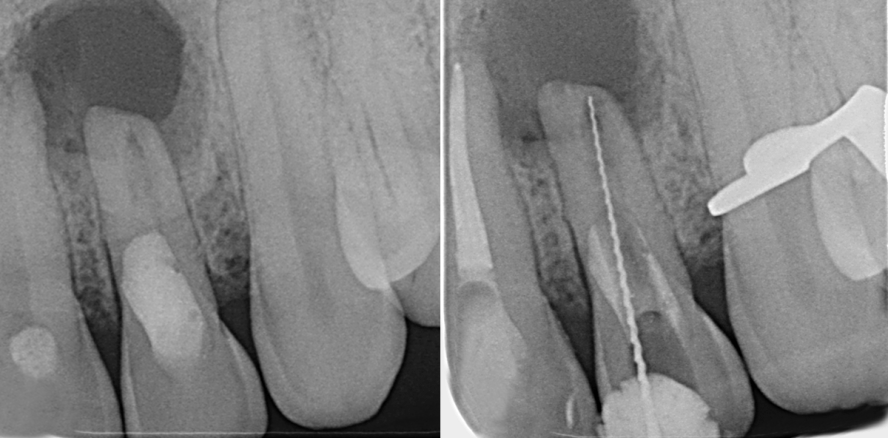

Bei der klinischen Untersuchung war an Zahn 21 ein provisorischer Trepanationsverschluss zu erkennen, Zahn 22 war auf der Palatinalfläche mit Komposit gefüllt. Beide Zähne reagierten nicht auf den Sensibilitätstest mit CO2-Schnee und waren perkussionsempfindlich. Außerdem war die Mobilität der Zähne 21 und 22 leicht erhöht (Grad I) und es lag eine druckdolente Schwellung im Vestibulum vor. Zur röntgenologischen Diagnostik wurden Einzelzahnaufnahmen der betroffenen Zähne angefertigt (Abb. 1). Hierbei ließ sich eine ausgeprägte, klar abgegrenzte apikale Radioluzenz mit ca. 9 mm Durchmesser ausgehend von Zahn 22 feststellen, die mit einer Abflachung der Wurzelspitze als Hinweis auf Resorptionsvorgänge einherging. Weiterhin war erkennbar, dass dieser seitliche Schneidezahn bis zur Hälfte der Wurzellänge großlumig mit einem röntgenopaken Material gefüllt worden war. Apikal davon ließ sich eine zunächst schmale, in Richtung apikal stark erweiterte Kanalstruktur erkennen.

Am geplanten Folgetermin für den Beginn der Revisionsbehandlung an Zahn 22 stellte sich der Patient abgesehen von einer leichten apikalen Druckdolenz schmerzfrei vor. Unter absoluter Trockenlegung mittels Kofferdam wurde die Zugangskavität angelegt. Als Nächstes erfolgte die Entfernung des Komposits aus dem Kanallumen unter Verwendung eines Operationsmikroskops. Im Bereich der Wurzelwände wurde Komposit belassen, um eine iatrogene Perforation zu vermeiden. In 15 mm Tiefe eröffnete sich apikal des mit Komposit verschlossenen Bereiches der nicht instrumentierte Abschnitt des Wurzelkanalsystems. Anschließend wurde der apikale Abschnitt mit Handfeilen in ISO-Größe 15 instrumentiert, wobei sich bei einer vorsichtigen Überinstrumentierung erneut Pus und Blut über den Kanal entleerten. Nach Spülung des Kanals mit steriler Kochsalzlösung wurde die Arbeitslänge endometrisch bestimmt und röntgenologisch verifiziert (Abb. 2). Es erfolgte die weitere Spülung des Kanals mit Natriumhypochlorit (NaOCl, 3 %). Nach Trocknung mit sterilen Papierspitzen wurde ein dünnfließendes, vorgemischtes Kalziumhydroxidpräpat eingebracht und der Zahn provisorisch adhäsiv verschlossen.